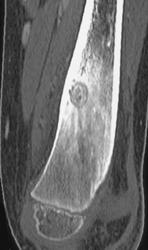

Tibial and Fibular Fractures Without Vascular Injury